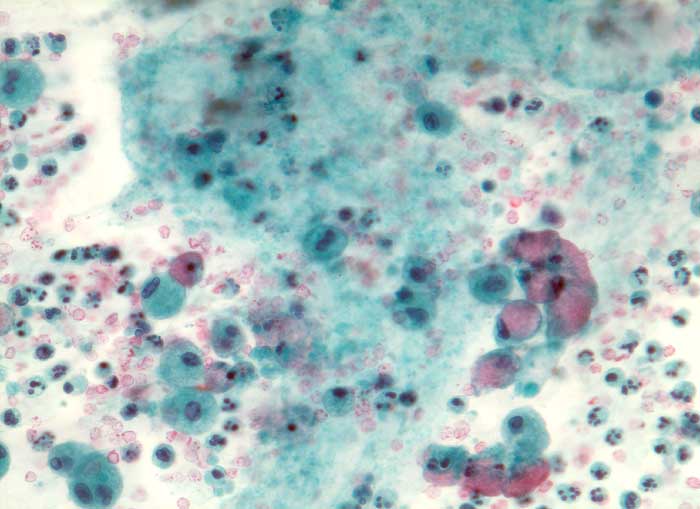

PathoPic – image database / PathoPic ID 5391 - Muzinöses Zystadenom

Muzinöses Zystadenom

Ovarialzysteninhalt: Neben reichlich frischem und älterem Blut mit neutrophilen Granulozyten sowie Makrophagen und Detritus hin und wieder becherzellartig aufgetriebene schleimbildende Zylinderzellen ohne Atypien

Schleim++

Altes Blut+

Granulozyten+

Histiozyten(+)

Makrophagen++

Histiozytäre Riesenzellen(+)

Schleimbildende Zylinderzellen(+)

Da hochdifferenzierte muzinöse Karzinome bisweilen kaum Atypien aufweisen, ist die sorgfältige Untersuchung des Operationspräparates notwendig (mindestens 1 Block pro cm Tumordurchmesser)

Zytologie

320